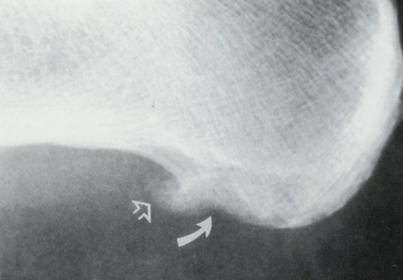

| What disease is this? What does the arrow indicate? | Rheumatoid arthritis. Arrow = Bone erosion secondary to inflammation of retrocalcaneal bursa. |